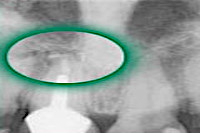

Wurzelspitzenresektion